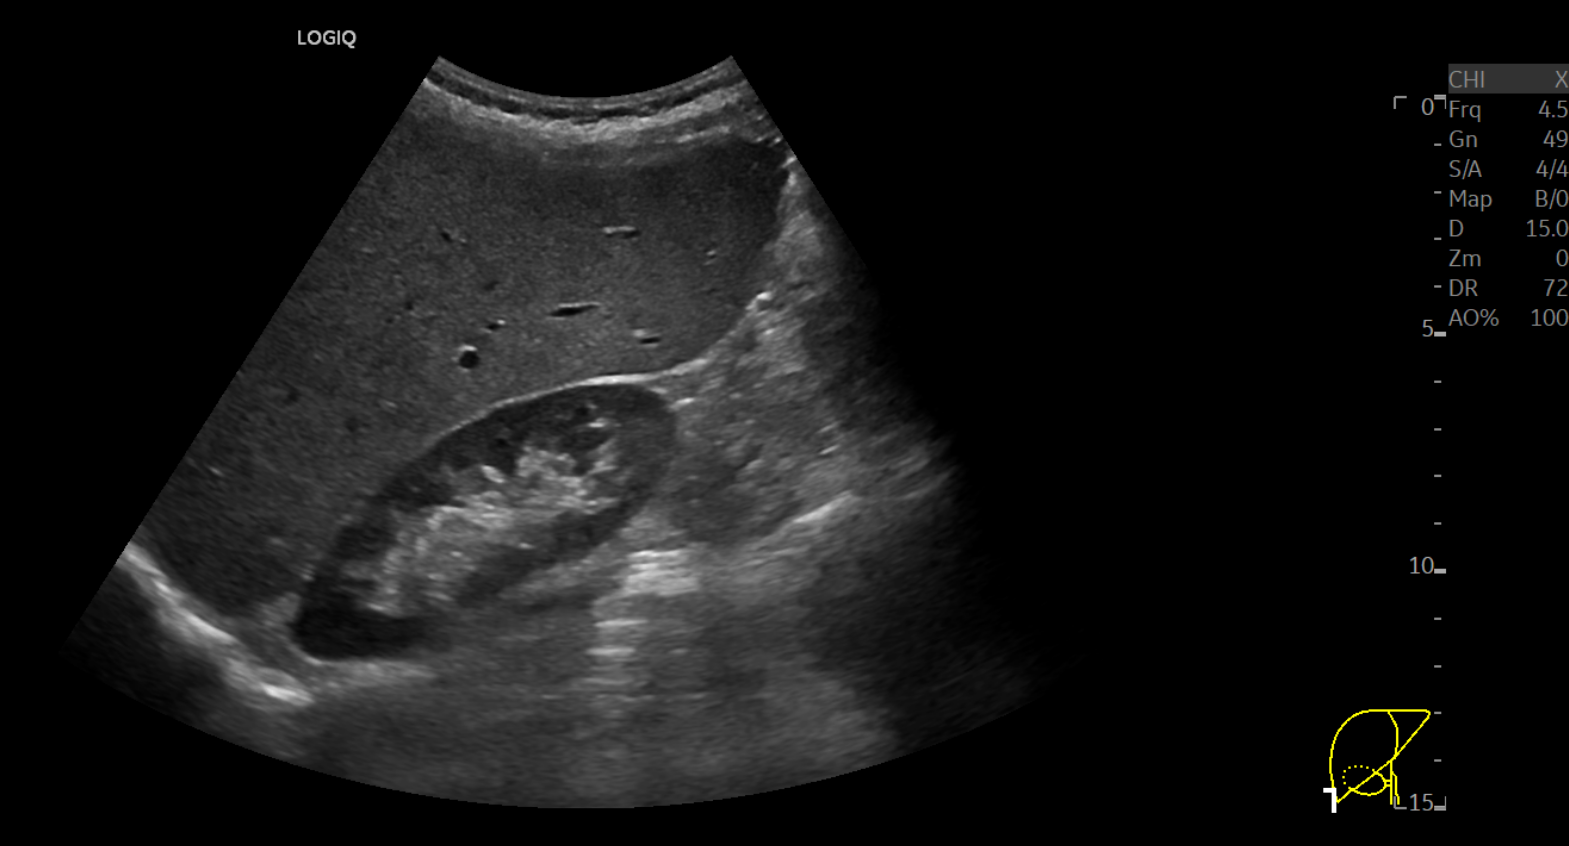

52세 남자환자로 알콜 의존증으로 꾸준히 술을 마시고 있습니다. 수년 전부터 계속 간수치 상승 및 만성 간염 진단을 받은 상태로, 최근 늑골골절로 내원하셔서 간초음파를 시행하셨습니다.

간초음파 B-mode 영상에서 거친 에코음영과 간 하연 둔화(inferior hepatic angle blunting)를 보여 전형적인 만성 간질환을 시사하고 있지만, 탄성초음파 상 탄성계수는 평균 4.3 kPa로 정상범주였으며, UGAP 정량분석에선 평균 0.58 dB/cm/MHz로 마찬가지로 정상범주 내였습니다.